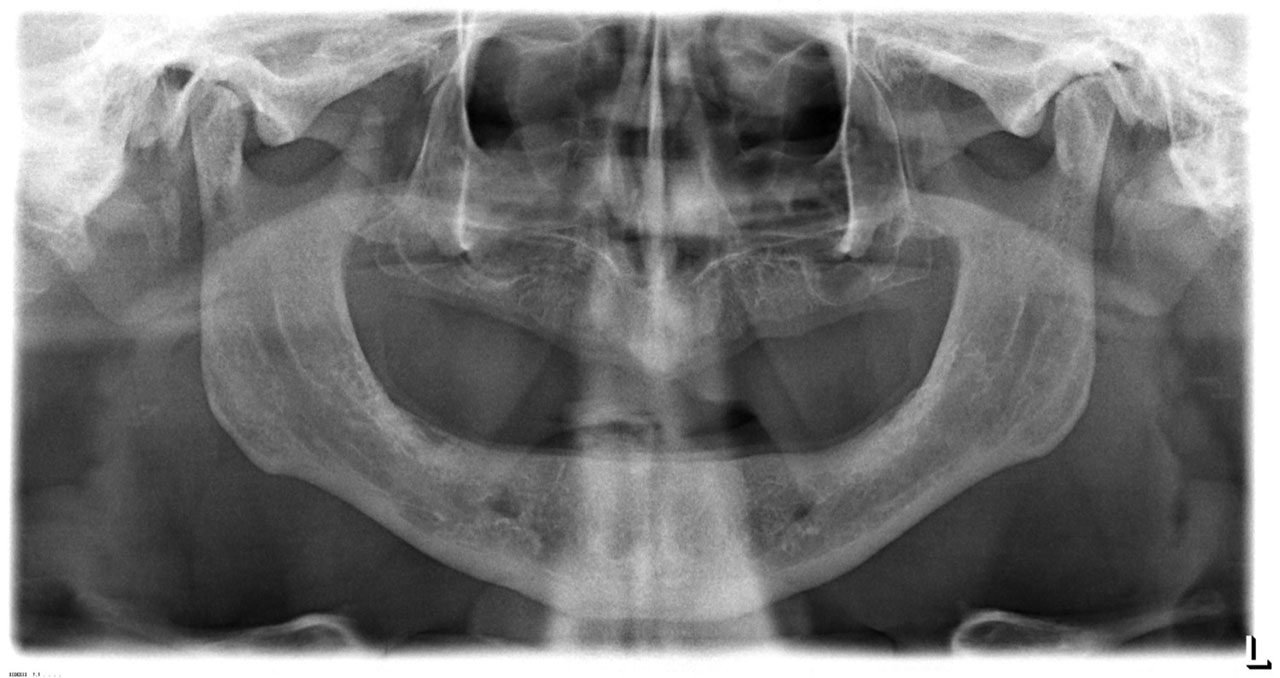

Sikerét mindenekelőtt a gyorsaságának köszönheti, hiszen a mai rohanó világban kinek van ideje, kedve fogatlanul otthon ülni heteket, hónapokat a fogpótlásra várva? Az Ihde implantációs eljárás során a páciens azonnal, de legkésőbb 72 óra múlva egy rögzített (tehát nem mozgó, nem kivehető) pótlással hagyja el a rendelőt. Ez az egyedülállóan gyors eljárás annak köszönhető, hogy azonnal tudunk implantálni szinte bárhova, akár foghúzás után is, továbbá a művelet nem jár nagy feltárásokkal, nincs szükség csontbeültetésre, így a gyógyulás folyamata is nagyon gyors és a beültetés technikájának köszönhetően maximum 72 óra múlva a korona is feltehető. Tehát ennyi idő alatt foga lesz a betegnek és az implantátum azonnal terhelhetővé is válik.

Az eljárás mellett szól az is, hogy nagyon biztonságos. A cég adatai alapján a beültetett implantátumok 98.2%-a sikeres. Az azonnali terhelésű implantátumokkal rögtön, akár foghúzás után is szinte bárhová lehet implantálni, bárkinek, legyen szó cukorbeteg, dohányos, vagy akár csontritkulásban szenvedő páciensről. Ennek köszönhető, hogy a betegek 99%-ánál alkalmazható a módszer.